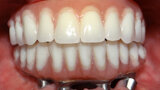

Fig. 10. Prótesis híbrida inmediata con 10 años de evolución y Rx Control a los 10 años.

Fig. 11. Prótesis híbrida inmediata con 10 años de evolución y Rx Control a los 10 años.